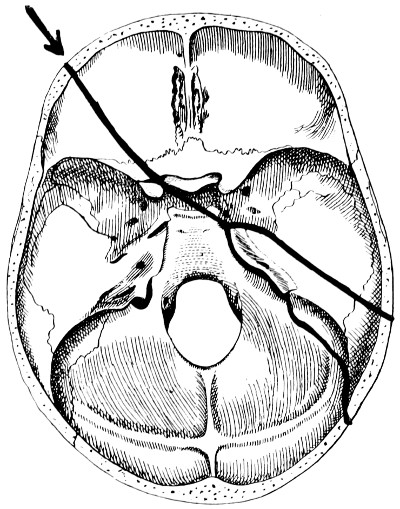

28. Illustrating the lines along which forces received on the vault are transmitted to the base 69

29 A and B. The base of the skull and the base as seen on transillumination 70, 71

30. Plan of the base of the skull 77

31. To illustrate the relation of basic fractures to cranial nerves 81

32-37. The lines pursued by basic fractures 83-8